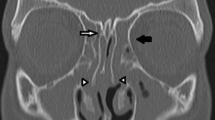

The MDCT produced the best HU uniformity at all dose levels, as the mean difference between the peripheral ROIs and the central ROI differed less than 10 HUs. Dental CBCT protocols produced differences in the range 50–60 HUs, whereas extremity CBCT had the worst uniformity, producing mean differences in the range 80–120 HUs. These differences in uniformity can also be visually appreciated (Fig. 3).

The extremity CBCT had the lowest LCV between the devices (LCV values of 0.48, 1.18 and 1.20 for ULD, LD and DF protocols, respectively). Comparing these to the values of dental CBCT (0.78, 1.43 and 2.51) and MDCT (1.14, 2.03 and 3.41) shows that the LD protocols of the other two devices had better LCV than the default (DF) protocol of the extremity CBCT. An explaining factor could be the visually appreciated cupping artefact in the extremity CBCT images (Fig. 5). The MDCT performed better than dental CBCT when similar protocols are compared head-to-head.

In clinics that have several comparable devices for scanning the same region, an objective and dose neutral assessment of image quality helps in choosing the primary method. In this study we aimed to compare the performance of the routinely used dental CBCT to an extremity CBCT and contemporary MDCT scanner in sinus imaging using protocols of equivalent radiation doses. The CBCT scanners had clearly superior image resolution compared to the MDCT, as seen qualitatively from the images and objectively from the MTFs. Thus, small findings with good inherent contrast, such as bony structures, are better visualized in CBCT images. However, the conventional MDCT provided superior contrast-to-noise ratio, low contrast visibility and image uniformity compared to the two CBCT scanners at similar dose levels. Hence, the MDCT should perform better in detection and characterization of findings with minor HU alterations. A bit surprisingly, the dose-matched sinus protocols of the extremity CBCT provided inferior image quality in all studied aspects as compared to the dental CBCT scanner. As such, the studied dental CBCT scanner should be preferred over the studied extremity CBCT scanner for sinus imaging.